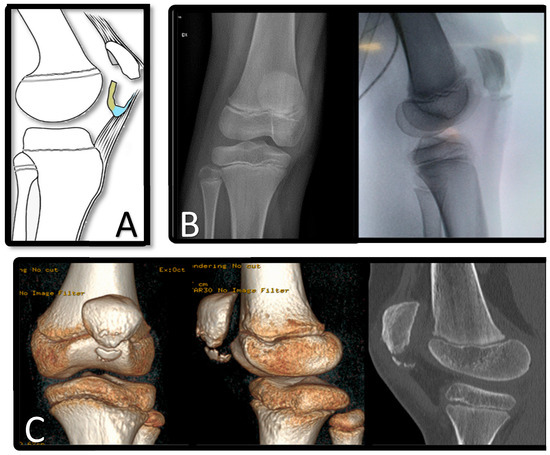

Patellar sleeve avulsion fractures are rare injuries seen in children between 8 and 12 years of age and are characterized by the separation of the cartilage “sleeve” from the ossified patella (Figure 1).

Figure 1. Representation of patellar sleeve fracture. (A): cartilage (yellow) and periosteum and cartilage (blue). (B): X-ray in antero-posterior and lateral view. (C): CT scan with 3D reconstruction.